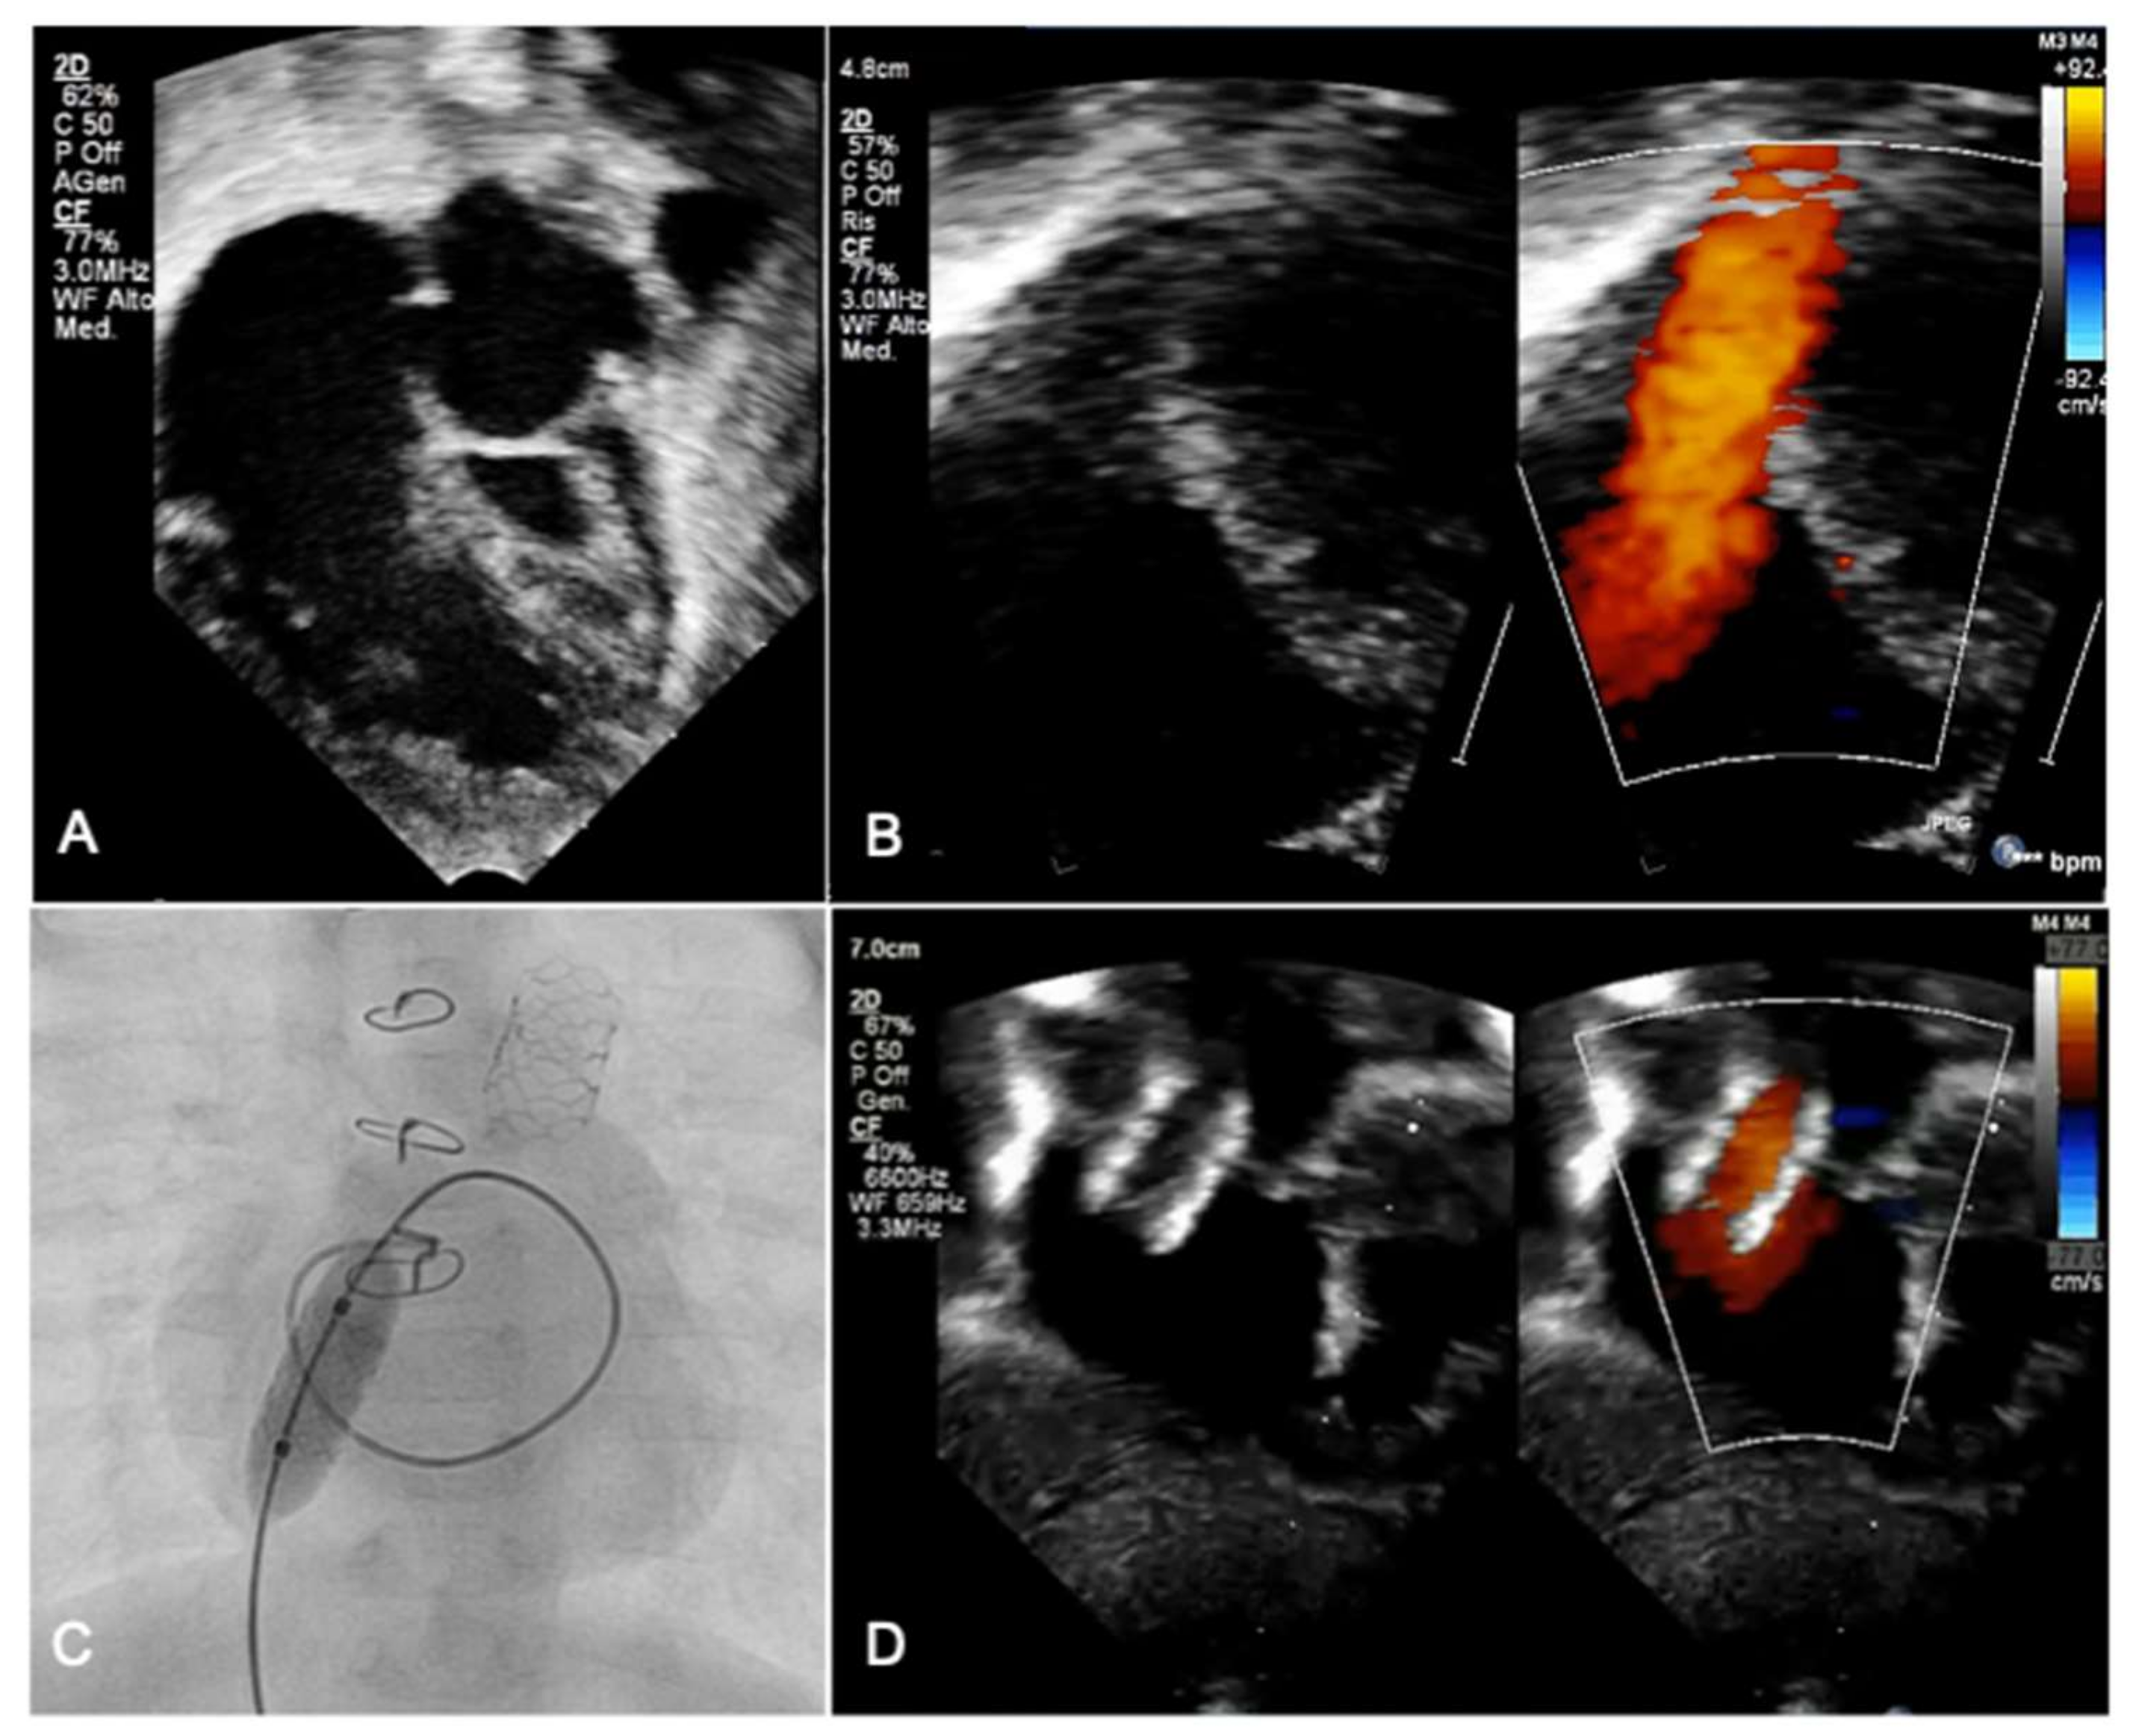

- Michel-Behnke, I.; Akintuerk, H.; Marquardt, I.; Mueller, M.; Thul, J.; Bauer, J.; Hagel, K.J.; Kreuder, J.; Vogt, P.; Schranz, D. Stenting of the ductus arteriosus and banding of the pulmonary arteries: Basis for various surgical strategies in newborns with multiple left heart obstructive lesions. Heart 2003, 89, 645–650. [Google Scholar] [CrossRef]

- Akintuerk, H.; Michel-Behnke, I.; Valeske, K.; Mueller, M.; Thul, J.; Bauer, J.; Hagel, K.J.; Kreuder, J.; Vogt, P.; Schranz, D. Stenting of the arterial duct and banding of the pulmonary arteries: Basis for combined Norwood stage I and II repair in hypoplastic left heart. Circulation 2002, 105, 1099–1103. [Google Scholar] [CrossRef] [PubMed]

- Galantowicz, M.; Cheatham, J.P.; Phillips, A.; Cua, C.L.; Hoffman, T.M.; Hill, S.L.; Rodeman, R. Hybrid approach for hypoplastic left heart syndrome: Intermediate results after the learning curve. Ann. Thorac. Surg. 2008, 85, 2063–2070; discussion 2070–2071. [Google Scholar] [CrossRef] [PubMed]

- Galantowicz, M.; Cheatham, J.P. Lessons learned from the development of a new hybrid strategy for the management of hypoplastic left heart syndrome. Pediatr. Cardiol. 2005, 26, 190–199. [Google Scholar] [CrossRef]

- Schranz, D.; Esmaeili, A.; Schrewe, R.; Kerst, G.; Akintuerk, H. Hypoplastic Left Heart Stage I: No Norwood, No Hybrid. Circulation 2020, 142, 1402–1404. [Google Scholar] [CrossRef] [PubMed]

- Goreczny, S.; Qureshi, S.; Rosenthal, E.; Krasemann, T.; Bedair, R.; Salih, C.; Austin, C.; Anderson, D.; Morgan, G.J. Self-expanding stent implantation in arterial duct during hybrid palliation of hypoplastic left heart syndrome: Midterm experience with a specially designed stent. EuroIntervention 2015, 10, 1318–1325. [Google Scholar] [CrossRef]

- Egan, M.J.; Hill, S.L.; Boettner, B.L.; Holzer, R.J.; Phillips, A.B.; Galantowicz, M.; Cheatham, J.P.; Kovalchin, J.P. Predictors of retrograde aortic arch obstruction after hybrid palliation of hypoplastic left heart syndrome. Pediatr. Cardiol. 2011, 32, 67–75. [Google Scholar] [CrossRef]

- Simsic, J.M.; Phelps, C.; Kirchner, K.; Carpenito, K.R.; Allen, R.; Miller-Tate, H.; Texter, K.; Galantowicz, M. Interstage outcomes in single ventricle patients undergoing hybrid stage 1 palliation. Congenit. Heart Dis. 2018, 13, 757–763. [Google Scholar] [CrossRef]

- Schranz, D.; Bauer, A.; Reich, B.; Steinbrenner, B.; Recla, S.; Schmidt, D.; Apitz, C.; Thul, J.; Valeske, K.; Bauer, J.; et al. Fifteen-year single center experience with the “Giessen Hybrid” approach for hypoplastic left heart and variants: Current strategies and outcomes. Pediatr. Cardiol. 2015, 36, 365–373. [Google Scholar] [CrossRef] [PubMed]